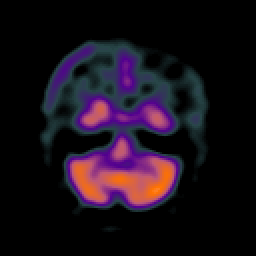

SPECT TC Study #1 -- Slice #14

[Home][Help][Clinical][Tour 1][Tour 2][Tour 3] Slice 14